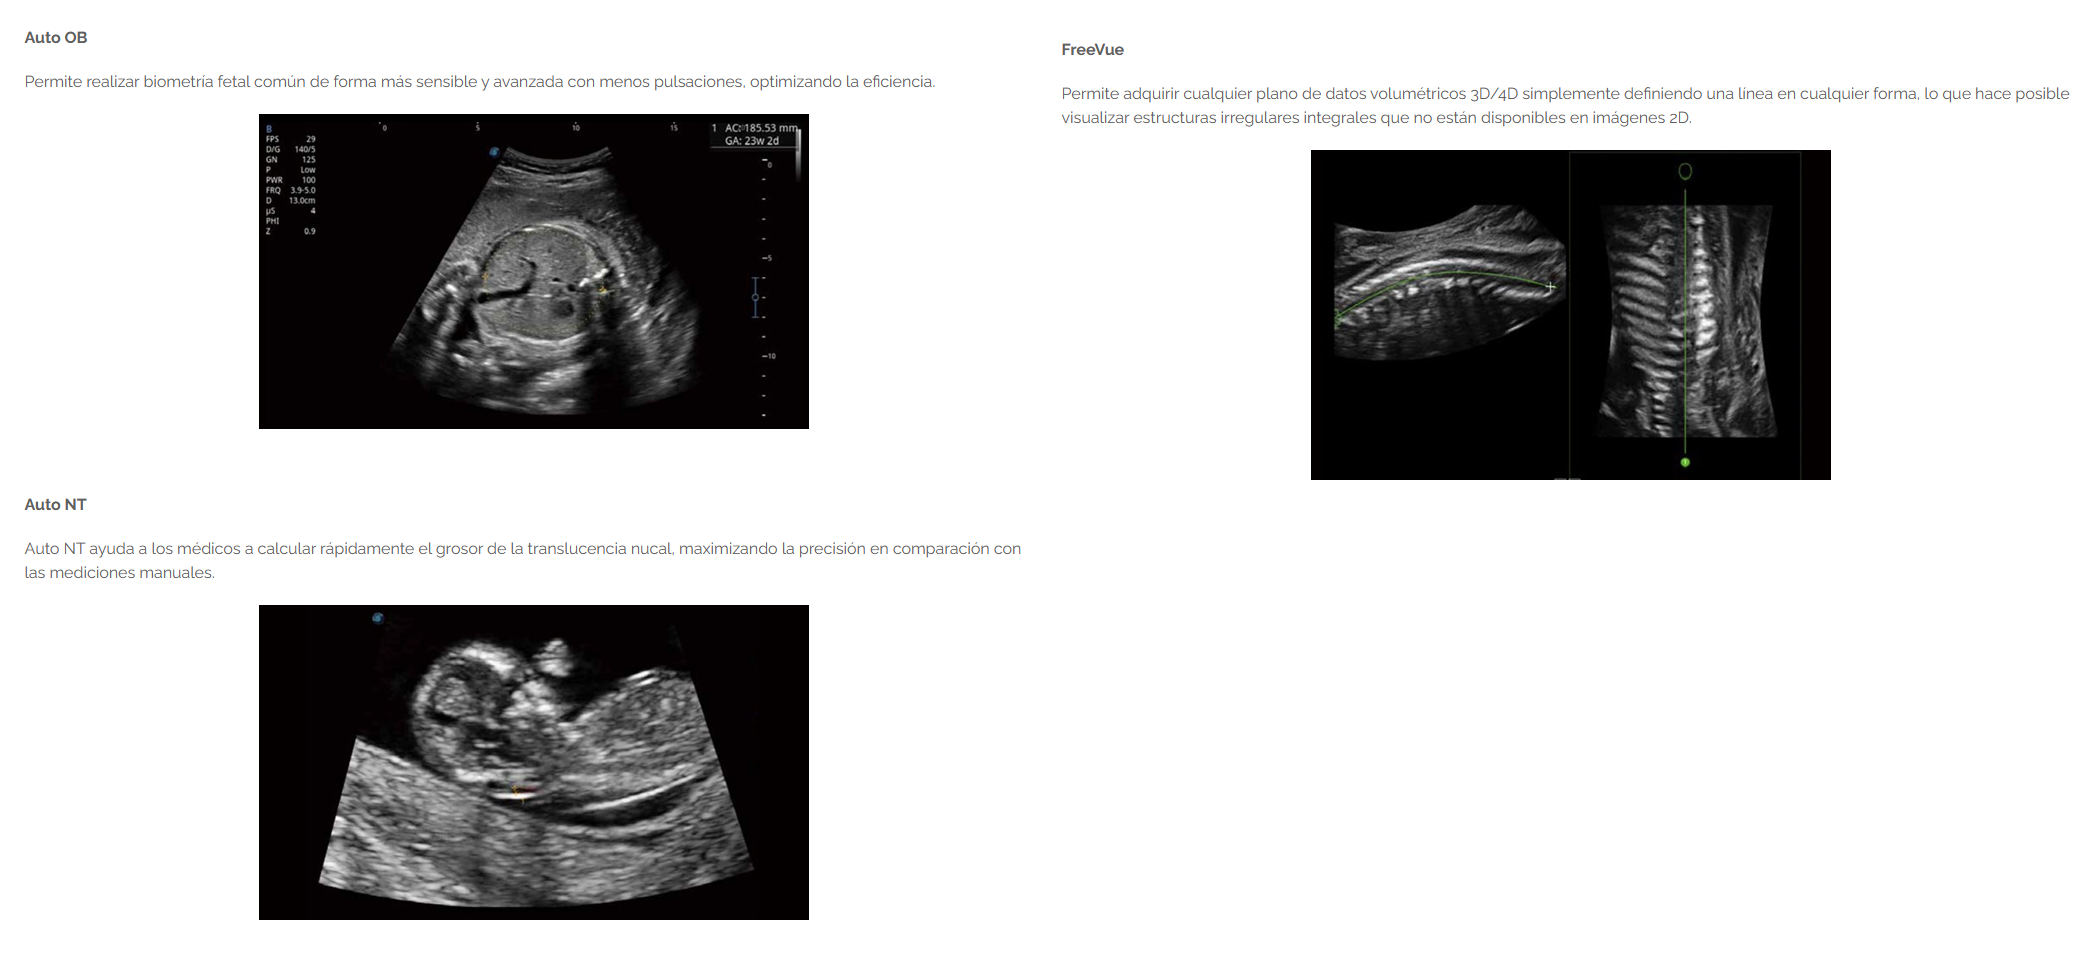

- Potente aplicación de obstetricia, que brinda atención dedicada a la mujer en 3D/4D desde los exámenes prenatales hasta el control del embarazo.